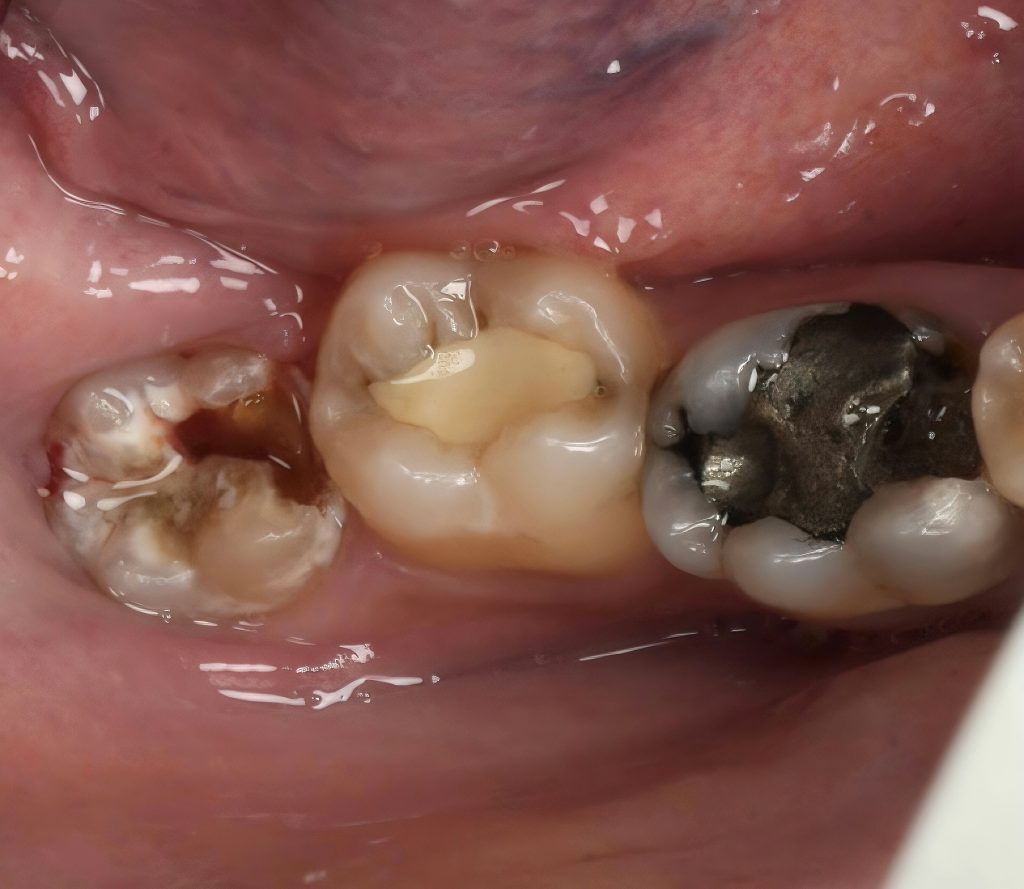

The patient presented with a distal carious lesion on a partially infra-occluded mandibular third molar exhibiting food impaction and sensitivity (Fig 1). CBCT and radiographs confirmed a deep Class II lesion extending sub-gingivally, but with adequate periodontal attachment for isolation and restoration.

Caries excavation performed conservatively, preserving enamel ridges. Distal sub-gingival margin elevated using the Matrix-within-Matrix DME technique with a sectional matrix system and Teflon-assisted adaptation. This enabled proper contact form and a cleansable margin (Fig 3).

- Fig 1: Pre-operative view showing distal caries on infra-occluded third molar.

- Fig 3: Deep marginal elevation with Matrix-within-Matrix technique.